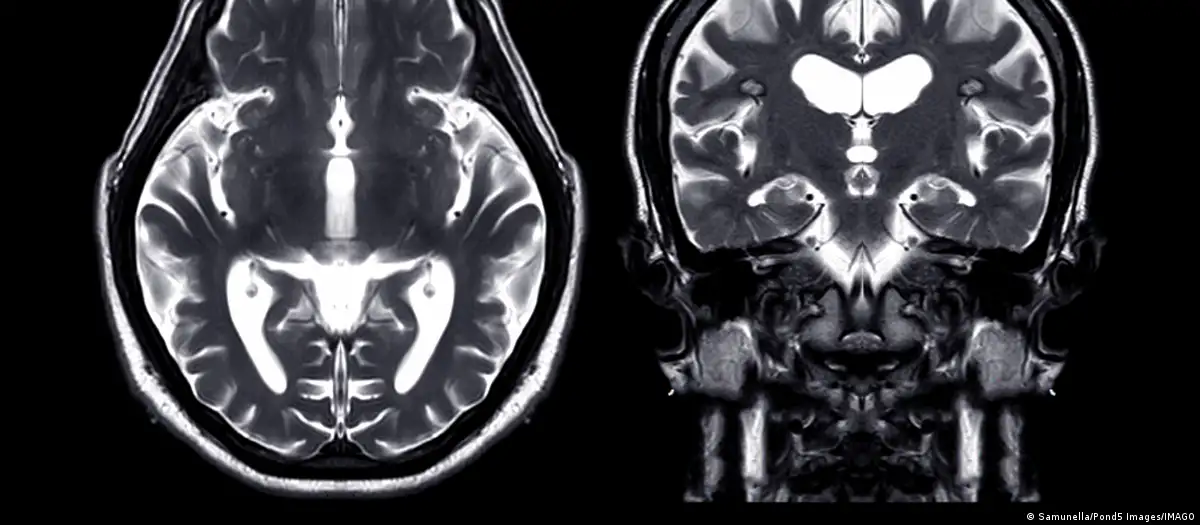

حدوث نزيف في الدماغ، حيث يُحتمل أن يكون النزيف قد ساهم في الخرفصورة من: Samunella/Pond5 Images/IMAGO

وفقًا لموقع "أخبار علوم الأعصاب" (Neuroscience News)، اكتشف العلماء من خلال دراسة بيانات 15 ألف مريض زيادة في حالات الخرف بعد حوالي 5.6 سنوات من حدوث نزيف في الدماغ، حيث يُحتمل أن يكون النزيف قد ساهم في الخرف نتيجة لتراكم مادة بيتا أميلويد أو تلف الأوعية الدموية. بناءً على هذه النتائج، يوصي الباحثون بضرورة إجراء فحوصات عقلية منتظمة للمرضى الذين تعرضوا للنزيف.

قال الدكتور صمويل بروس الباحث الأول في الدراسة، إن النزيف الدماغي يزيد بشكل واضح من خطر الإصابة بالخرف، بغض النظر عن نوعه. وبناءً على ذلك، هذا يعني أن الأشخاص الذين تعرضوا لنزيف دماغي يجب أن يخضعوا لفحوصات منتظمة لفحص وظائفهم الإدراكية، إذ إن ذلك قد يساعد في اتخاذ قرارات بشأن رعايتهم المستقبلية.

من خلال استخدام بيانات التأمين من برنامج ميديكير بين عامي 2008 و2018، درس الدكتور بروس وزملاؤه حالة حوالي 15,000 شخص تعرضوا لأنواع مختلفة من النزيف الدماغي. على الرغم من أن النزيف قد يحدث بسببإصابات في الرأس، إلا أنهم ركزوا على الحالات التي تحدث بشكل عفوي.

وقد وجدوا أن هؤلاء المرضى كانوا أكثر عرضة للإصابة بالخرف بعد حوالي 5.6 سنوات من النزيف مقارنة بأكثر من مليوني شخص لم يتعرضوا لنزيف.

وفقًا لدراسة أجراها باحثو جامعة ويل كورنيل، شملت مجموعة كبيرة من كبار السن في الولايات المتحدة، تبين أن النزيف داخل الجمجمة يضاعف خطر الإصابة بالخرف. وقد لوحظ هذا الخطر بشكل مستمر عبر مختلف أنواع النزيف داخل الجمجمة.